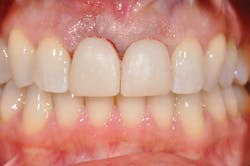

Figure 2: Prior to procedures, teeth appeared healthy with no clinical signs of trauma.

Figure 6: Immediate-load temporaries are finished.

My periodontist looked at me and said my case would require an oral and maxillofacial surgeon to do a surgical extraction and that he could not place an implant for me. Argh. I love my periodontist, yet understand that this is why there are many different types of specialists. Clearly, with so little root left, this tooth was going to shatter imminently if not certainly during the extraction process. My general dentist then informed me that she, too, would prefer I see a prosthodontist as this was going to potentially change my entire smile. I was now dealing with a full bag of emotions, meeting a new team for restoration (see Figure 2).

Through the entire procedure I was completely comfortable physically-no pain, only pressure. Truth is, when there is a gaping hole in the front of your mouth, it's a crazy feeling every time you swallow. My mouth was numb but my tongue could totally feel the absence, and my brain could imagine a train driving through this giant gap. Temporaries going in, shade chosen ... in hindsight recommend that your patients whiten to their desired shade in advance if there is time because this will be a forever shade (see Figure 6). I was numb for several hours, took three ibuprofen, and antibiotics which I had started two days prior. That evening, brushing was frightening but I felt nothing, literally nothing! The false tooth and tissue and my entire premaxilla was numb, void of all feeling. While it meant pain meds were unnecessary, it was disconcerting to have nothing there. I chose to use only plastic cups and silverware and eat completely soft foods. The temporaries are for appearance only, and mine were stunning, but they are not, not, not to be used for biting. This time is for healing and permanent restorations are not scheduled for 12-16 weeks.